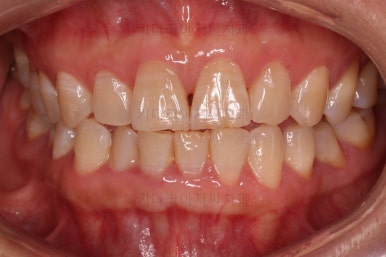

전후사진을 비교해보겠습니다.

쓰러진 치아도 원위치로 만들어 기능을 회복시켜주었고, 임플란트도 1개로 마무리를 할 수 있었어요.

이렇게 단순히 임플란트를 해야지 하는 상황도 간단한 교정치료와 병행한다면 치아도 아끼고 임플란트도 줄이는 매우 좋은 부산교정치료 될 수 있답니다.